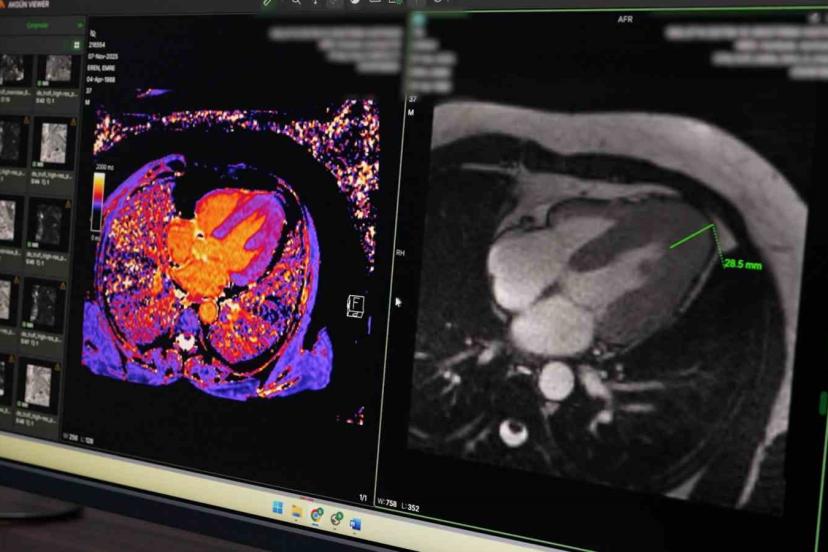

Hastanede uygulanan koroner BT anjiyografi yöntemiyle kalp damarlarının girişimsel işleme gerek kalmadan görüntülenebildiğini belirten Petik, bu sayede hastaların klasik anjiyografi öncesinde detaylı şekilde değerlendirilebildiğini ifade etti. Yeni başlatılan kardiyak MR uygulamasının da kalp kası ve kapak hastalıklarının tanısında önemli katkı sunduğunu dile getirdi.

Örnek bir vakaya da değinen Petik, kardiyak MR sayesinde nadir görülen bir kalp kası hastalığının erken dönemde tespit edilerek hastaya uygun tedavi planlamasının yapıldığını ifade etti. Petik, yapılan yatırımlar ve güçlü teknik altyapıyla Malatya Eğitim ve Araştırma Hastanesi’nin ileri görüntüleme alanında bölgesel merkez olma yolunda önemli mesafe kat ettiğini belirterek, vatandaşların başka illere gitmeden nitelikli sağlık hizmetine ulaşmasının hedeflendiğini söyledi.